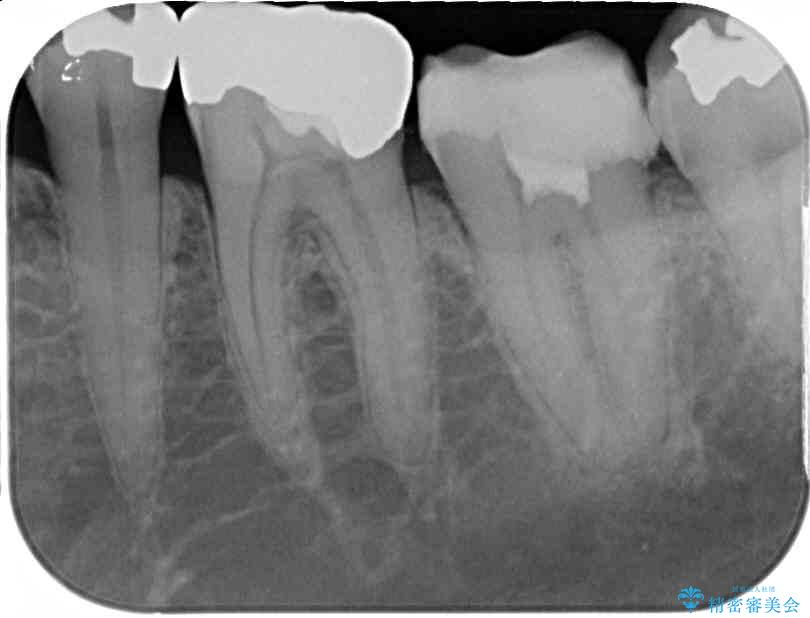

歯質の欠損が大きいため、処置後はオールセラミッククラウンにて補綴治療を行うこととしました。

虫歯は深くまで進行しており、歯冠部の神経から出血が認められました。神経を部分的に除去したところ出血が治まったので、生体親和性の非常に高いセメントにて充填し、仮封をしました。

後日状態を確認したところ、残された神経に異常は認められませんでした。

治療後

• 治療をしても違和感の続く奥歯 神経を極力残した虫歯治療 治療後画像